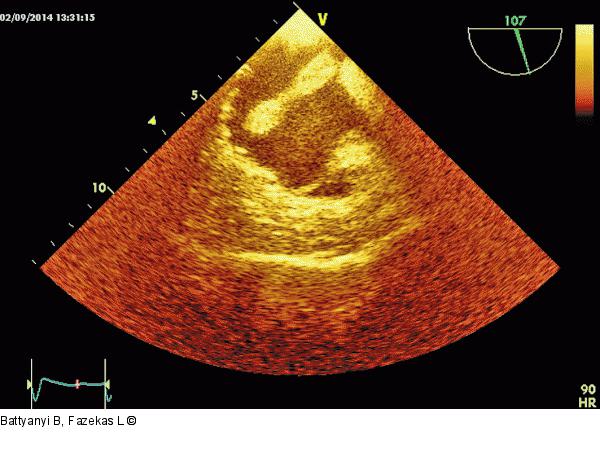

Abbildung 4: Thromboembolus Thromboembolus im rechten Vorhof (modifizierter bikavaler Schnitt). |

Thromboembolus im rechten Vorhof (modifizierter bikavaler Schnitt). |